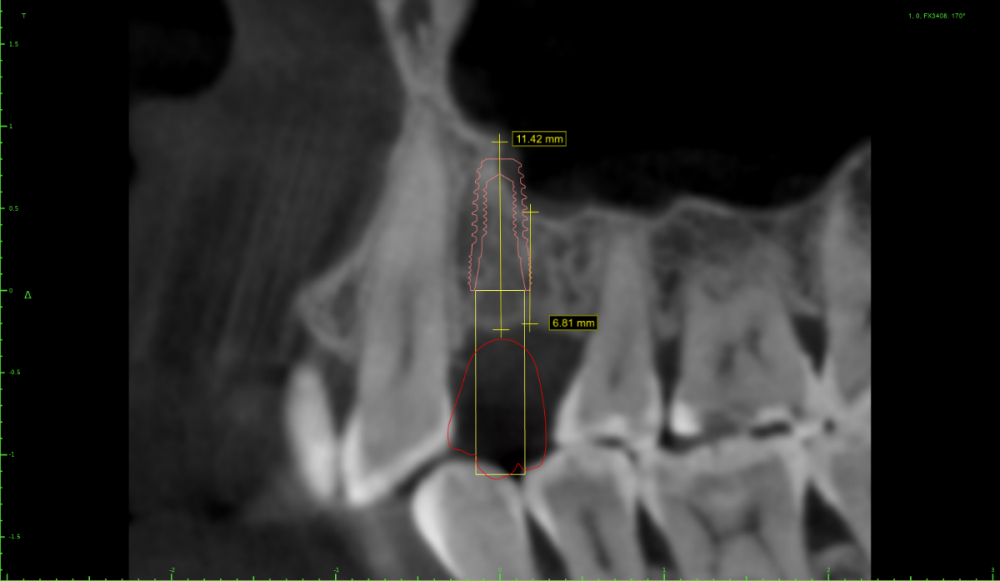

Irouil Опубликовано 4 мая, 2021 Поделиться Опубликовано 4 мая, 2021 (изменено) Тут стучать вообще не обязательно, просто пилотным сверлиться и экспандером расшириться. Если исходит из этого положения винта а если пойти ортодоксальнее и сместить его дистальнее, то ничего там при стуке не отломается Изменено 4 мая, 2021 пользователем Irouil Ссылка на комментарий

АнтонТЛТ Опубликовано 4 мая, 2021 Поделиться Опубликовано 4 мая, 2021 4.0*7.3 синус не нужен, нужна нкр Ссылка на комментарий

Irouil Опубликовано 4 мая, 2021 Поделиться Опубликовано 4 мая, 2021 (изменено) Не очень понял, что не так в предложенном автором вопроса варианте расстановки и зачем переходить на вариант с НКР и винтом 4.0? Изменено 4 мая, 2021 пользователем Irouil Ссылка на комментарий

АнтонТЛТ Опубликовано 4 мая, 2021 Поделиться Опубликовано 4 мая, 2021 Винт 4.0 потому что в данной системе, которую я поставил он 7.3мм, диаметром 3.5 только 8.5мм и более. У автора 3.6 на 7мм как я понял) Автор установил имплантат очень глубоко, чтобы избежать нкр и близко к клыка. Какой будет профиль прорезывания и что будет с костным пиком через несколько месяцев после протезирования? Ссылка на комментарий

Irouil Опубликовано 4 мая, 2021 Поделиться Опубликовано 4 мая, 2021 У меня нет дома просмотрщика с модельками, поэтому скриншотов не будет, но в целом соглашусь - нужно НКР. И вертикальный синус) Правда НКР несложная, дефект практически трехстеночный. На уровне платформы больше 3.5 мм не вижу ширину гребня Ссылка на комментарий

Женька Опубликовано 5 мая, 2021 Поделиться Опубликовано 5 мая, 2021 @АнтонТЛТ неа, 3.5*8 Можно конечно вариант который я ранее предлагал 7мм винт из которых 1.5мм полированная шейка. Но с НКР её(шейку) не совместить я так понимаю. Ссылка на комментарий